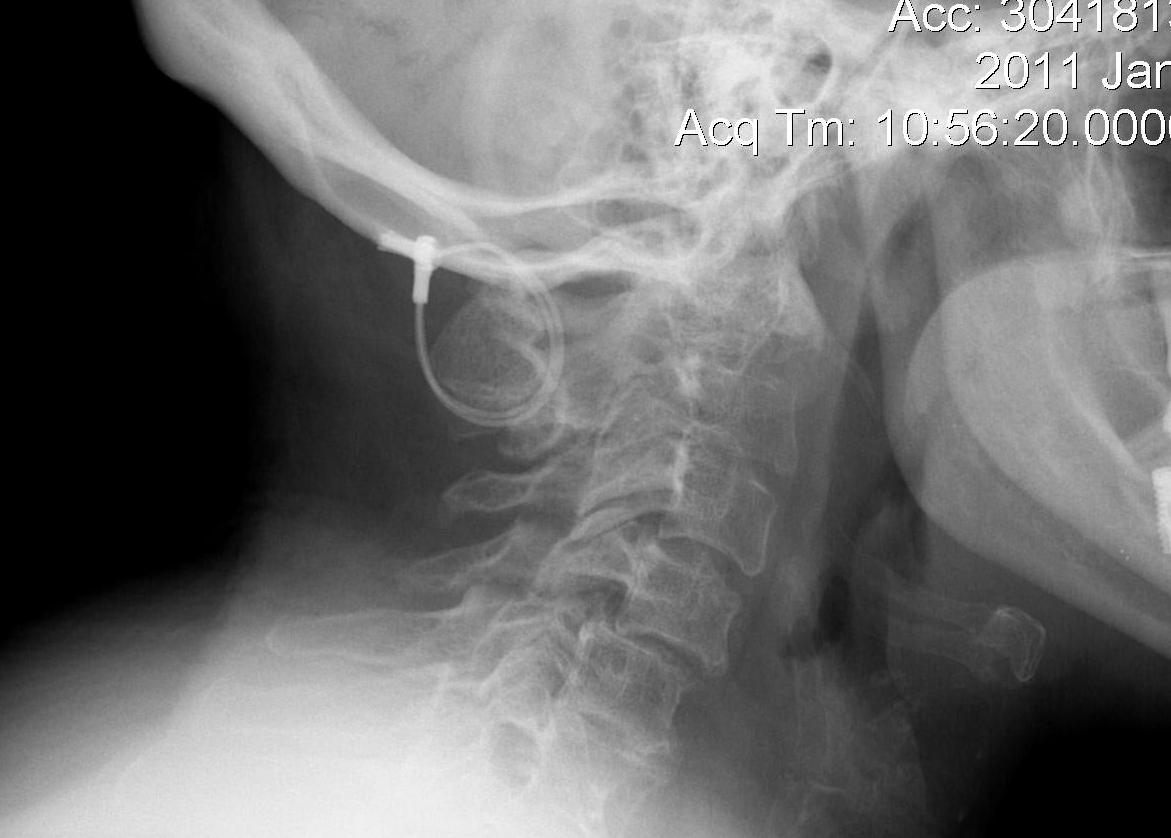

Basilar invagination / Vertical subluxation

Definition

Superior migration of the odontoid into foramen magnum

Pathology

Due to erosion of lateral masses of atlas and occipital condyles

- can lead to compression of brain stem

- risk of myelopathy / sudden death

- associated with severe peripheral disease

Diagnosis

Ranawat measurement < 13 mm

- line between anterior and posterior arch C1

- centre of pedicle of C2

McCrae

- line of foramen magnum

- tip of odontoid should not protrude above this line

McGregor line > 4.5 mm

- line hard palate to posterior occiput

- if tip of dens > 4.5 mm above this line = vertical settling

- severe > 8 men or > 10 women

CT

Coronal and sagittal CT of basilar invagination